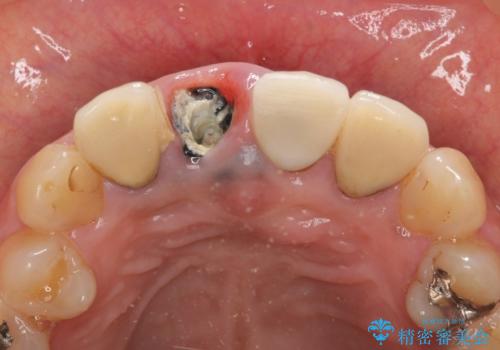

- 右上の前歯が折れてしまったので診て欲しいといらっしゃった方の症例です。

右上1番目の歯は保存不可能だったため抜歯し、ブリッジによる補綴を行いました。